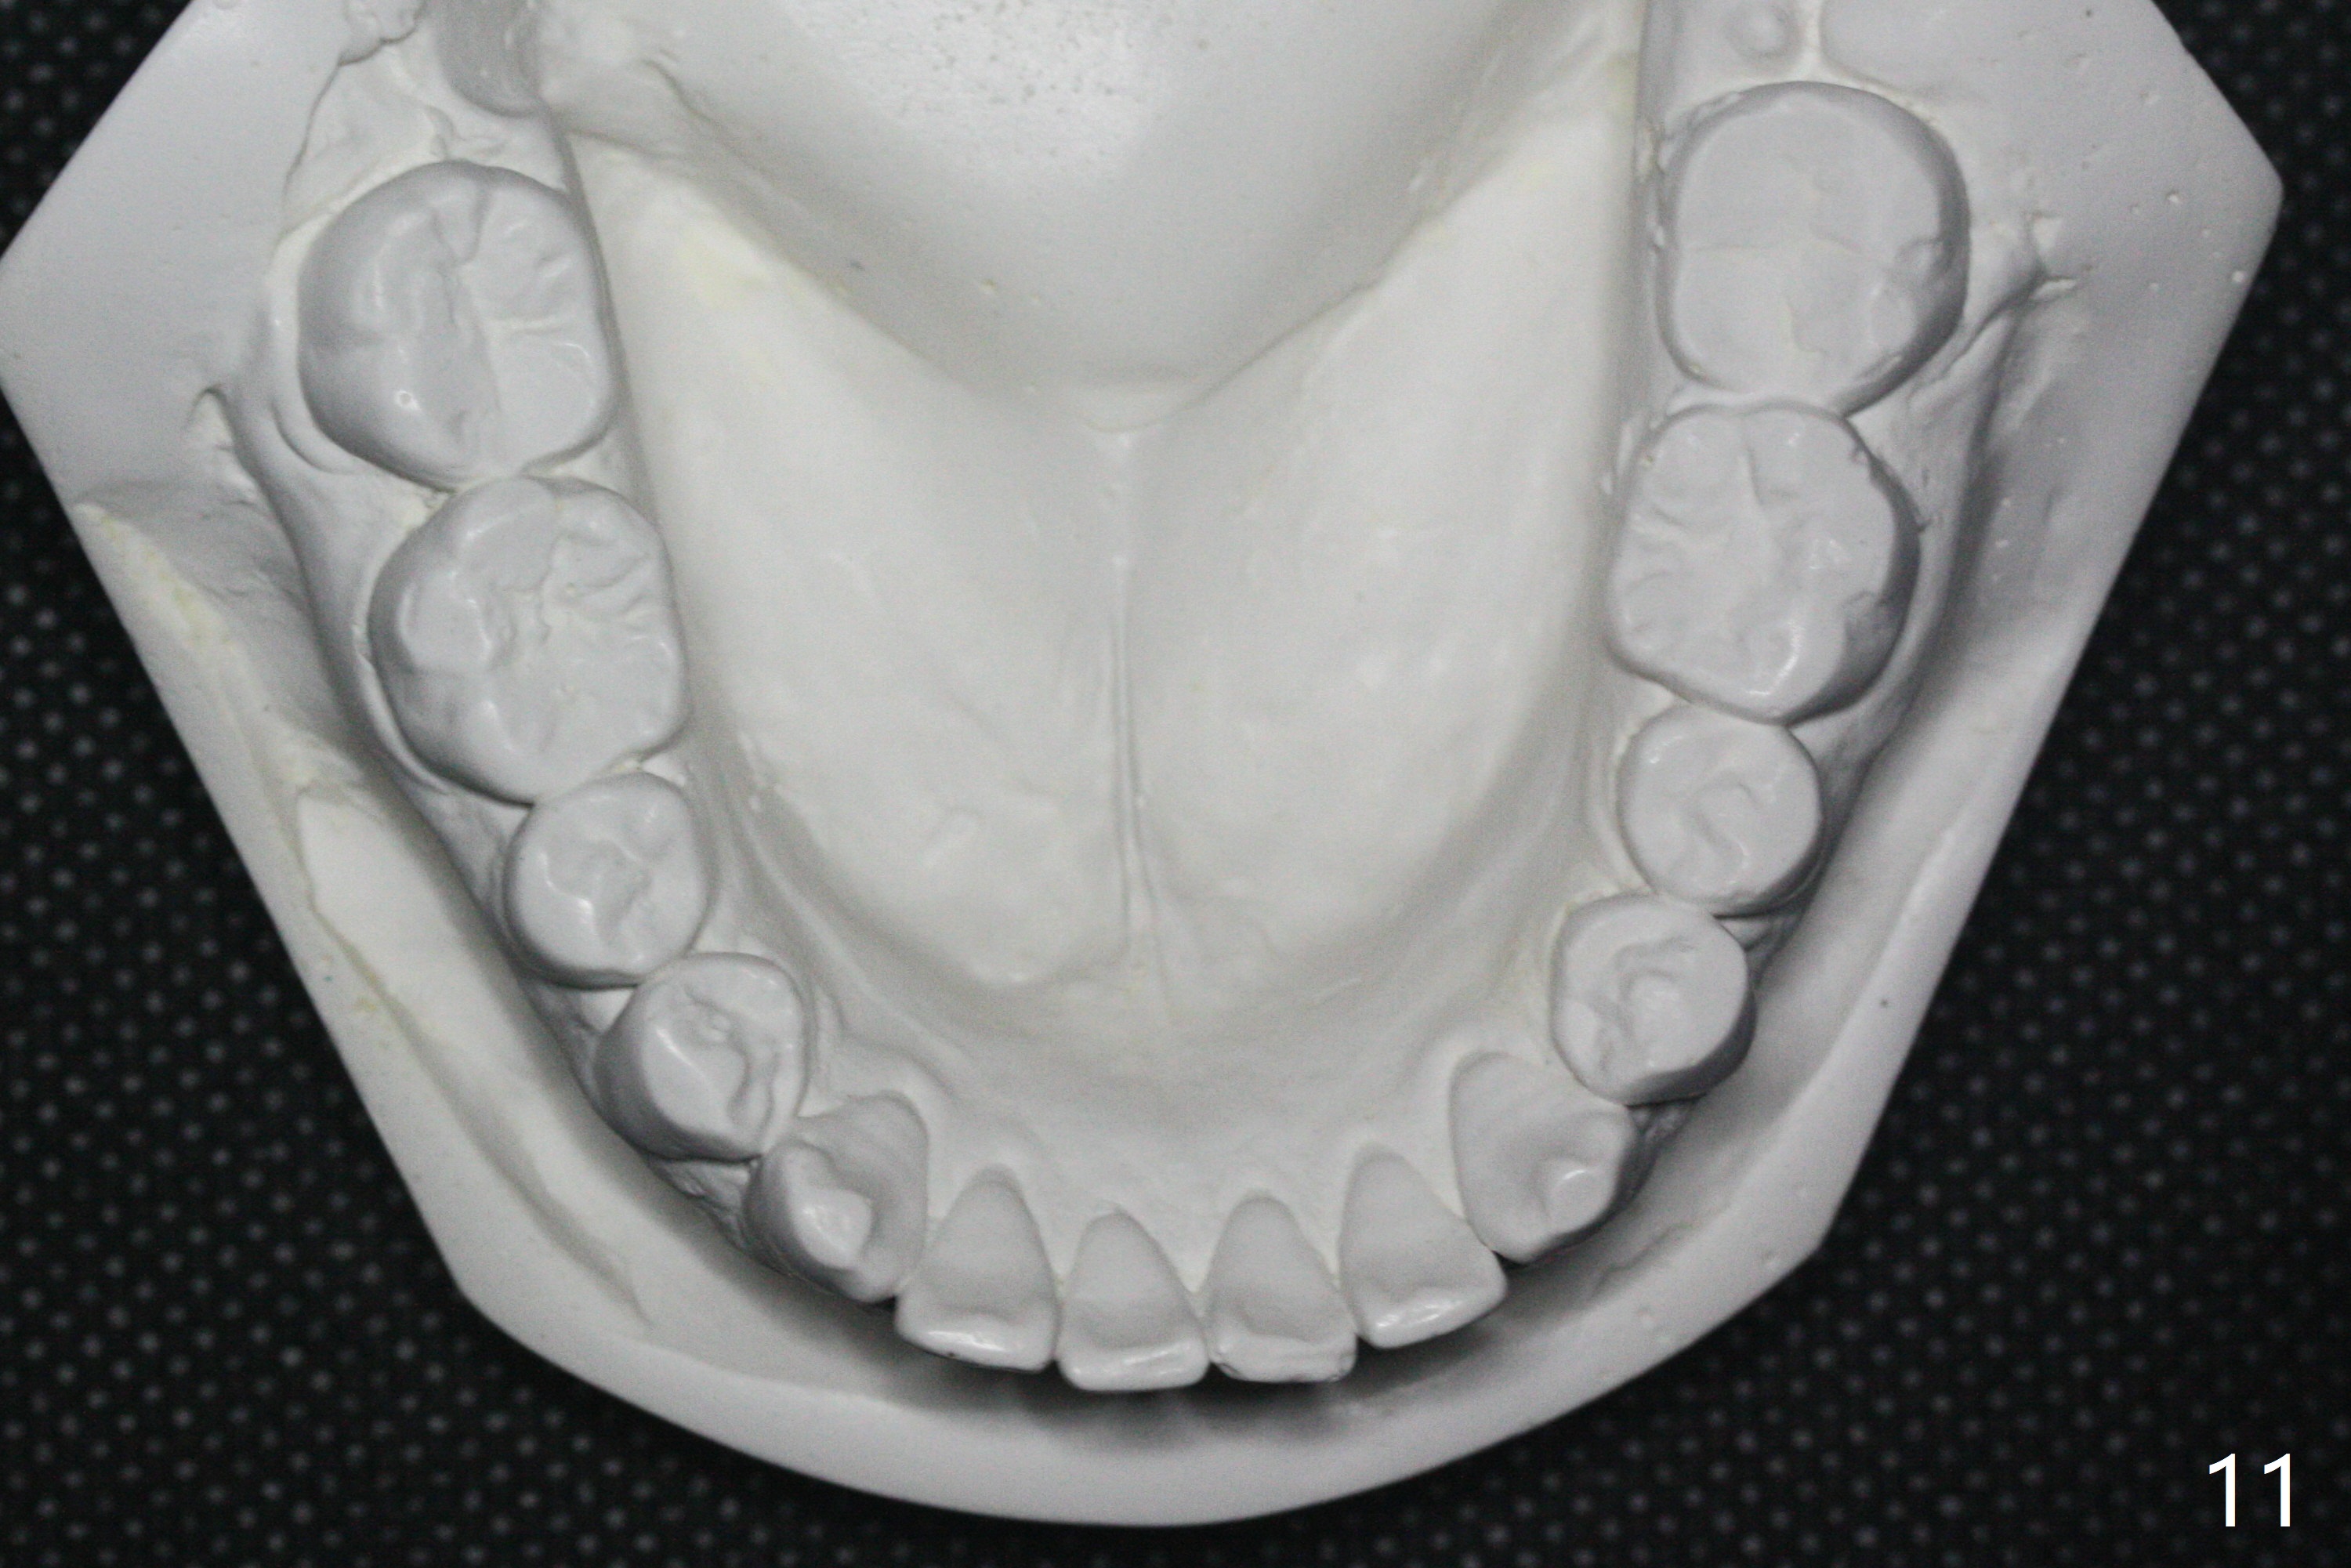

A 40-year-old man requests orthodontics after #17 and 32 extraction. UL5 is missing (Fig.1), while the upper midline deviates to the left (Fig.2 arrow) with crowding between UL2 and 3 (Fig.3). The main goal is to retract UL5 distal and move the upper midline to the right to alleviate UL anterior crowding. Implant will be not needed. To monitor potential root resorption associated with tooth movement, preop PAs are taken (Fig.4-7). The space for an implant at UR5 is narrow. UR4 needs to be distalized using UR7 or a miniimplant distal to UR7 as an anchor (Fig.8). UR4 and 3 will be repositioned to establish Class I occlusion (Fig.9). The space gained by UR4 distalization may be enough to correct the upper midline deviation and UL3 malposition (Fig.10). Brackets will be placed in the lower arch in spite of the normal alignment (Fig.11). UL2 and 3 brackets are unable to be engaged to 14 niti wire (Fig.12). Next visit try to engage UL2 bracket. If not, save the old wire for possible future reuse. Closed spring is placed with 18 ss wire <3 months post banding (coronavirus). Three weeks post closed spring between UR4-7, UR3,4 are being distalized (Fig.13). Distalization of UR4 is not much in 5.5 months (Fig.14,15). It seems necessary to use a miniimplant distal to UR7 as an anchor (Fig.16 white circle), place a long hook mesial to UL4 (more or less root movement instead of tilt) and place the same closed spring between the anchor and hook. In spite of the fact that UR4 seems to have been completely distalized and that UR2 is being distalized 8 months post banding (Fig.18), a 8 mm long mini-implant is placed in the maxillary tuberosity with minimal local anesthetic (Fig.17,19). A longer closed spring (18 mm) is placed between the implant and UR3 hook (Fig.20). Next appointment a lingual button will be placed at UR4 for rotation, while a post hook mesial to UR3 for torque. UR3 distalizes with the help of UR mini-implant, which is unfortunately loose. Next visit place lingual button at UR4 (Fig.21 arrow) to distalize the lingual cusp. Crimpable power hook is placed mesial to UR2 for distalization (for root torque, Fig.22). If it works, remove the wire and reposition the hook for UR1 next visit. UR2 is distalized in one appointment (~ 1 month, Fig.23, as compared to Fig.22). With lingual button at UR4, rotation seems to have been corrected shortly (Fig.24 arrow).